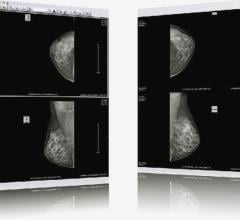

Despite decades of progress in breast imaging, one challenge continues to test even the most skilled radiologists ...

The current body of research supporting digital breast tomosynthesis (DBT or 3-D mammography) is now overwhelming, with ...